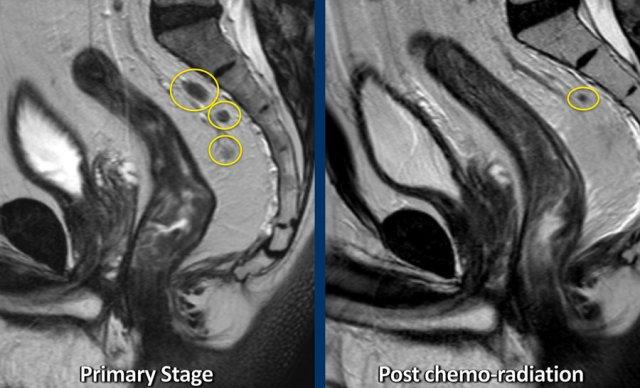

Ví dụ về Hình ảnh

- Hình ảnh T2-weighted phân giai đoạn ban đầu và phân giai đoạn lại cho thấy vùng nền khối u chủ yếu xơ hóa với tín hiệu không đồng nhất nhỏ (mrTRG 3) sau hóa xạ trị.

- Hình ảnh DWI tái giai đoạn cho thấy vùng tín hiệu cao khu trú tại bờ trong của xơ hóa, với tín hiệu ADC thấp, cho thấy sự khuếch tán bị hạn chế.

- Mô bệnh học xác nhận đây là phần mô u còn sót lại nhỏ (ypT2)

- Trước CRT:Xâm lấn MRF lan rộng từ vị trí 4–8 giờ (mũi tên).

- Sau CRT:Khối u đã trải qua quá trình xơ hóa và co rút khỏi MRF. Một lớp mỡ hiện đã có thể nhìn thấy, với chỉ một vài sợi xơ nhỏ—cho thấy MRF không có khối u tại thời điểm đánh giá lại (yMRF-).